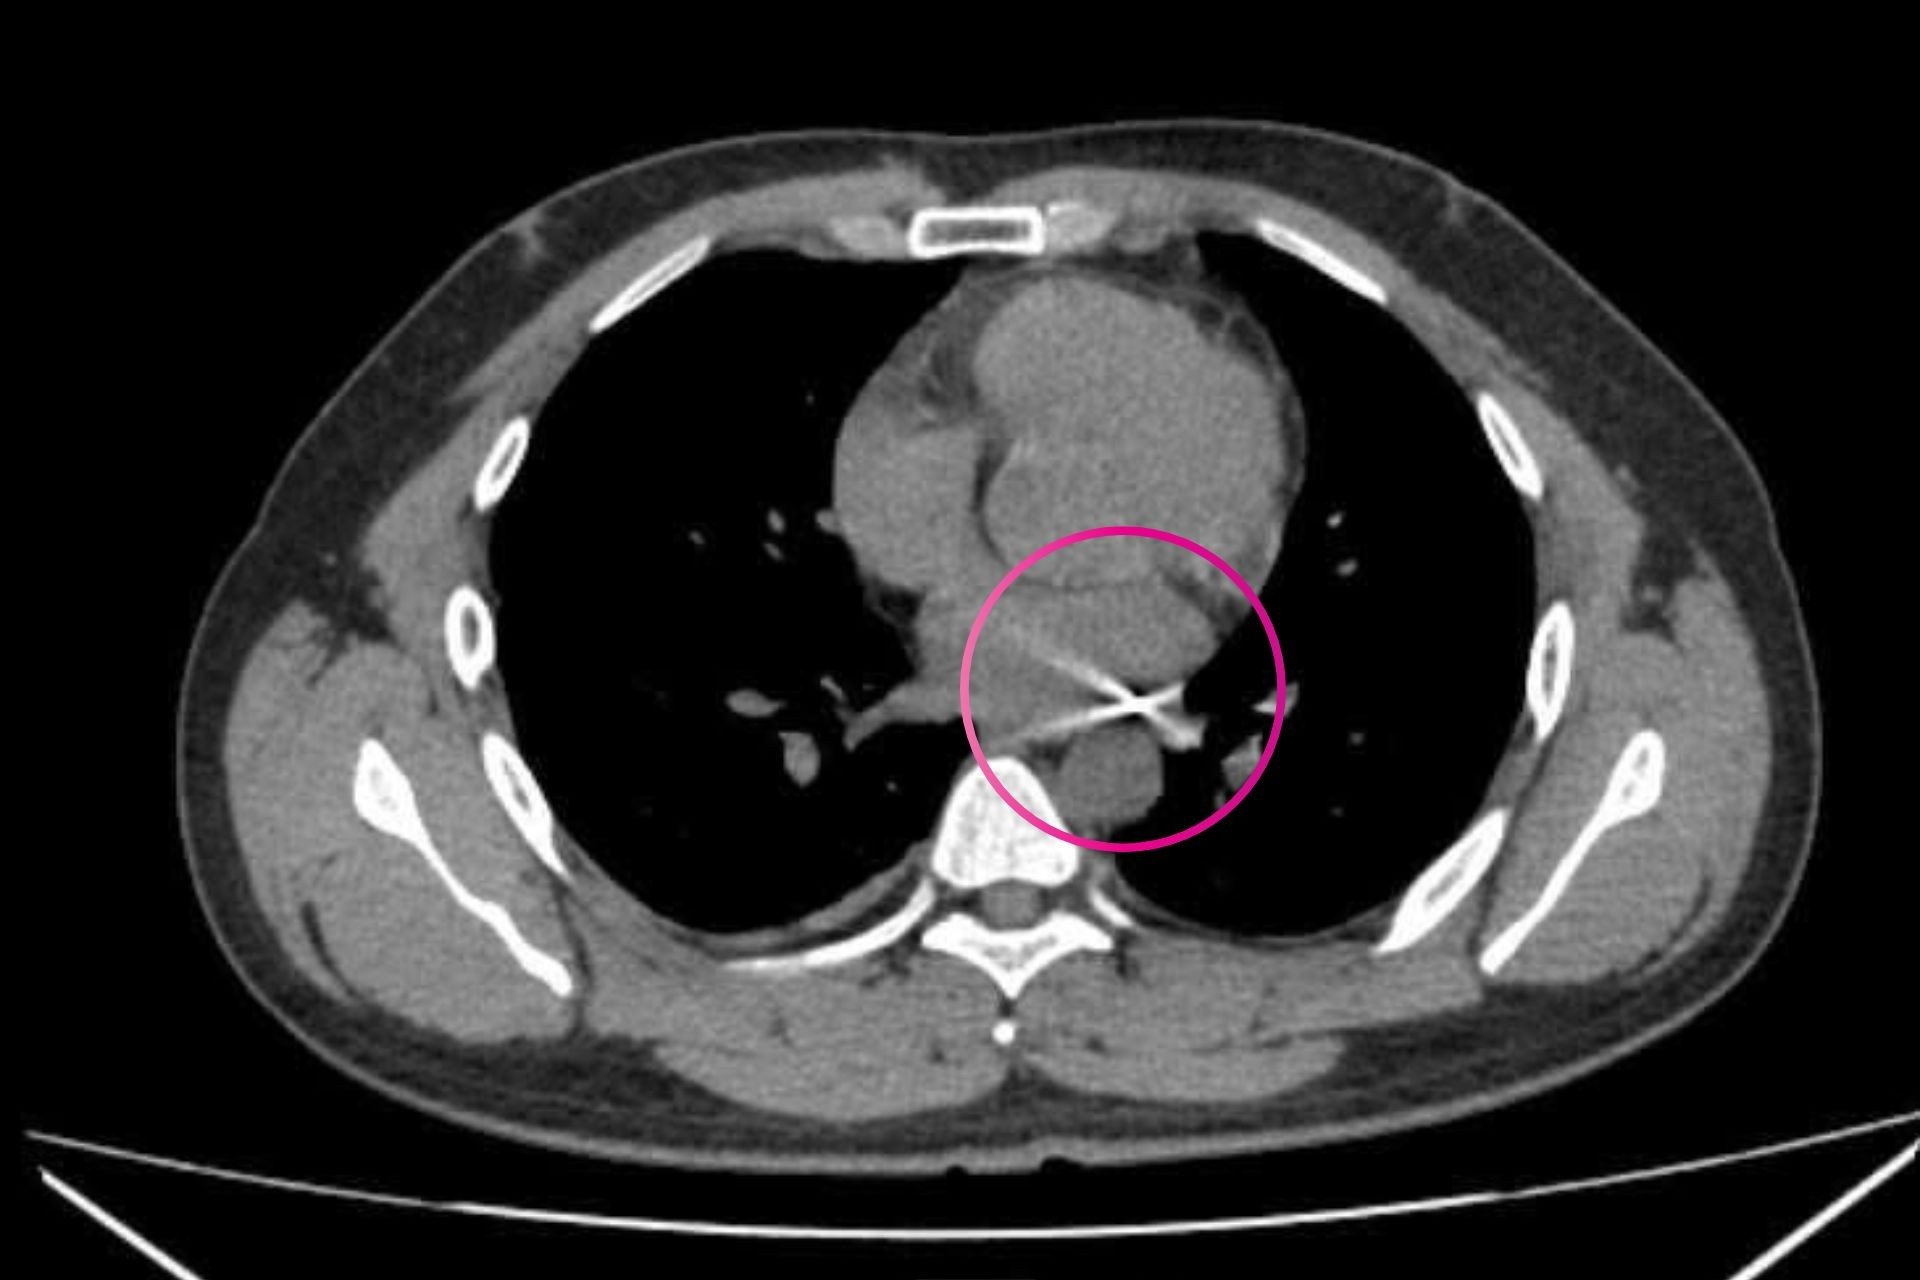

Qua thăm khám ban đầu, các bác sĩ xác định viên đạn đi từ phía sau lưng bên phải xuyên sang bên trái, tạo nên đường đi phức tạp, áp sát nhiều cấu trúc quan trọng trong lồng ngực.

Trong quá trình mổ, ê-kíp phải thận trọng bóc tách quanh khu vực động mạch chủ ngực. Sau khi xác định vùng này an toàn, các bác sĩ quyết định mở màng ngoài tim để tiếp cận dị vật. Tại đây, đầu đạn được phát hiện nằm kẹt ở vị trí giữa động mạch chủ và động mạch phổi – một điểm cực kỳ nguy hiểm.

Sau hơn 4 giờ nỗ lực, ê-kíp đã lấy thành công viên đạn có kích thước khoảng 0,3 x 0,5 cm ra khỏi cơ thể bệnh nhân. Các bác sĩ cho biết, dù kích thước nhỏ, nhưng chỉ cần lệch vị trí vài milimet hoặc bỏ sót dị vật, nguy cơ tổn thương tim và các mạch máu lớn có thể dẫn đến tử vong.